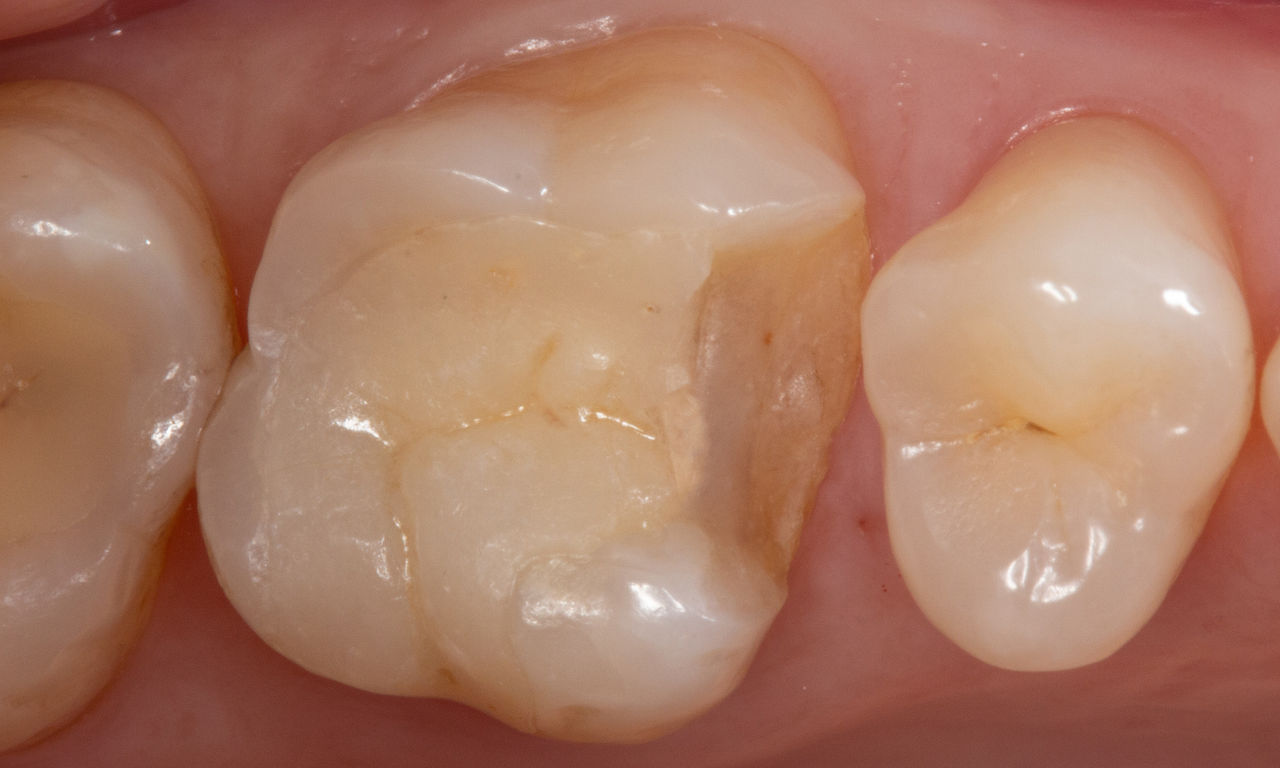

Before: Failed amalgam restoration needing replacement. Patient complaining of sensitivity and tooth presenting multiple cracks.

After: Chairside CAD/CAM partial crown restoration fabricated with CEREC Tessera Advanced Lithium-Disilicate glass ceramic.